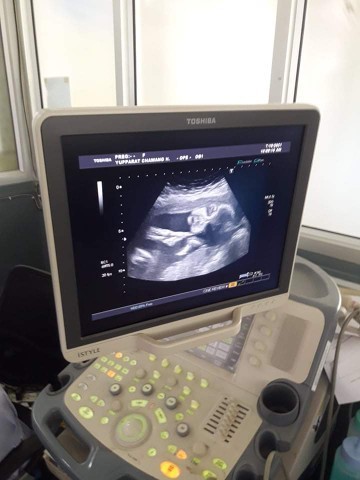

ภาพอัลตร้าซาวด์

ไหนลองๆเอาภาพซาวด์หน้าตรงมาอวดกันหน่อยค่ะ มีคนบอกว่าภาพอัลตร้าซาวด์ก็หน้าเหมือนกันหมด เหมือนกันจริงป่าวน๊า?? ของเราตอน31w